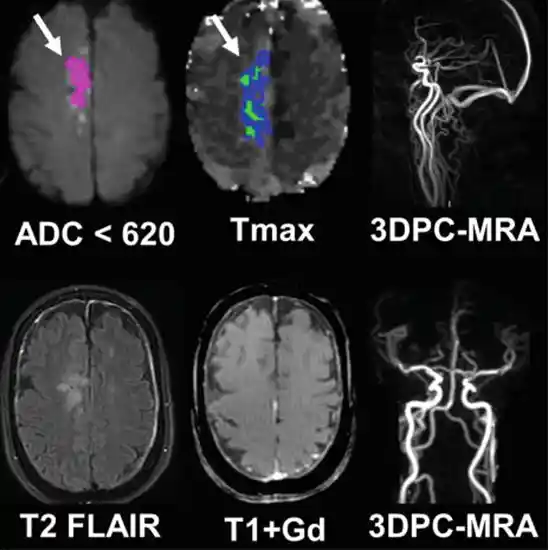

DWI (DIFFUSION WEIGHTED IMAGING) Brain is based upon the random Brownian motion of water molecules. This sequence is particularly used for tumor characterization and cerebral ischemia.

MRA(Magnetic Resonance Angiography)Brain is an examination to visualize the blood vessels of the brain. The detail provided is so prominent that the contrast dye study can be omitted.

The above combination of MRI Screening of Brain+DWI+MRA+Neck examination is done when there is a tumor present in the brain or the neck. It is used to see if the blood vessels are affected by the tumor and used for detecting cerebral ischemia(an acute medical condition where there is very less blood flow passing in the brain)

MRI Screening of Brain+DWI+MRA+Neck  is recommended to detect the presence of a tumor in the brain or the neck and to see if the blood vessels (MRA) are affected by the tumor. It is also used to detect cerebral ischemia. It is an acute medical condition where there is very less blood flow passing through the brain.